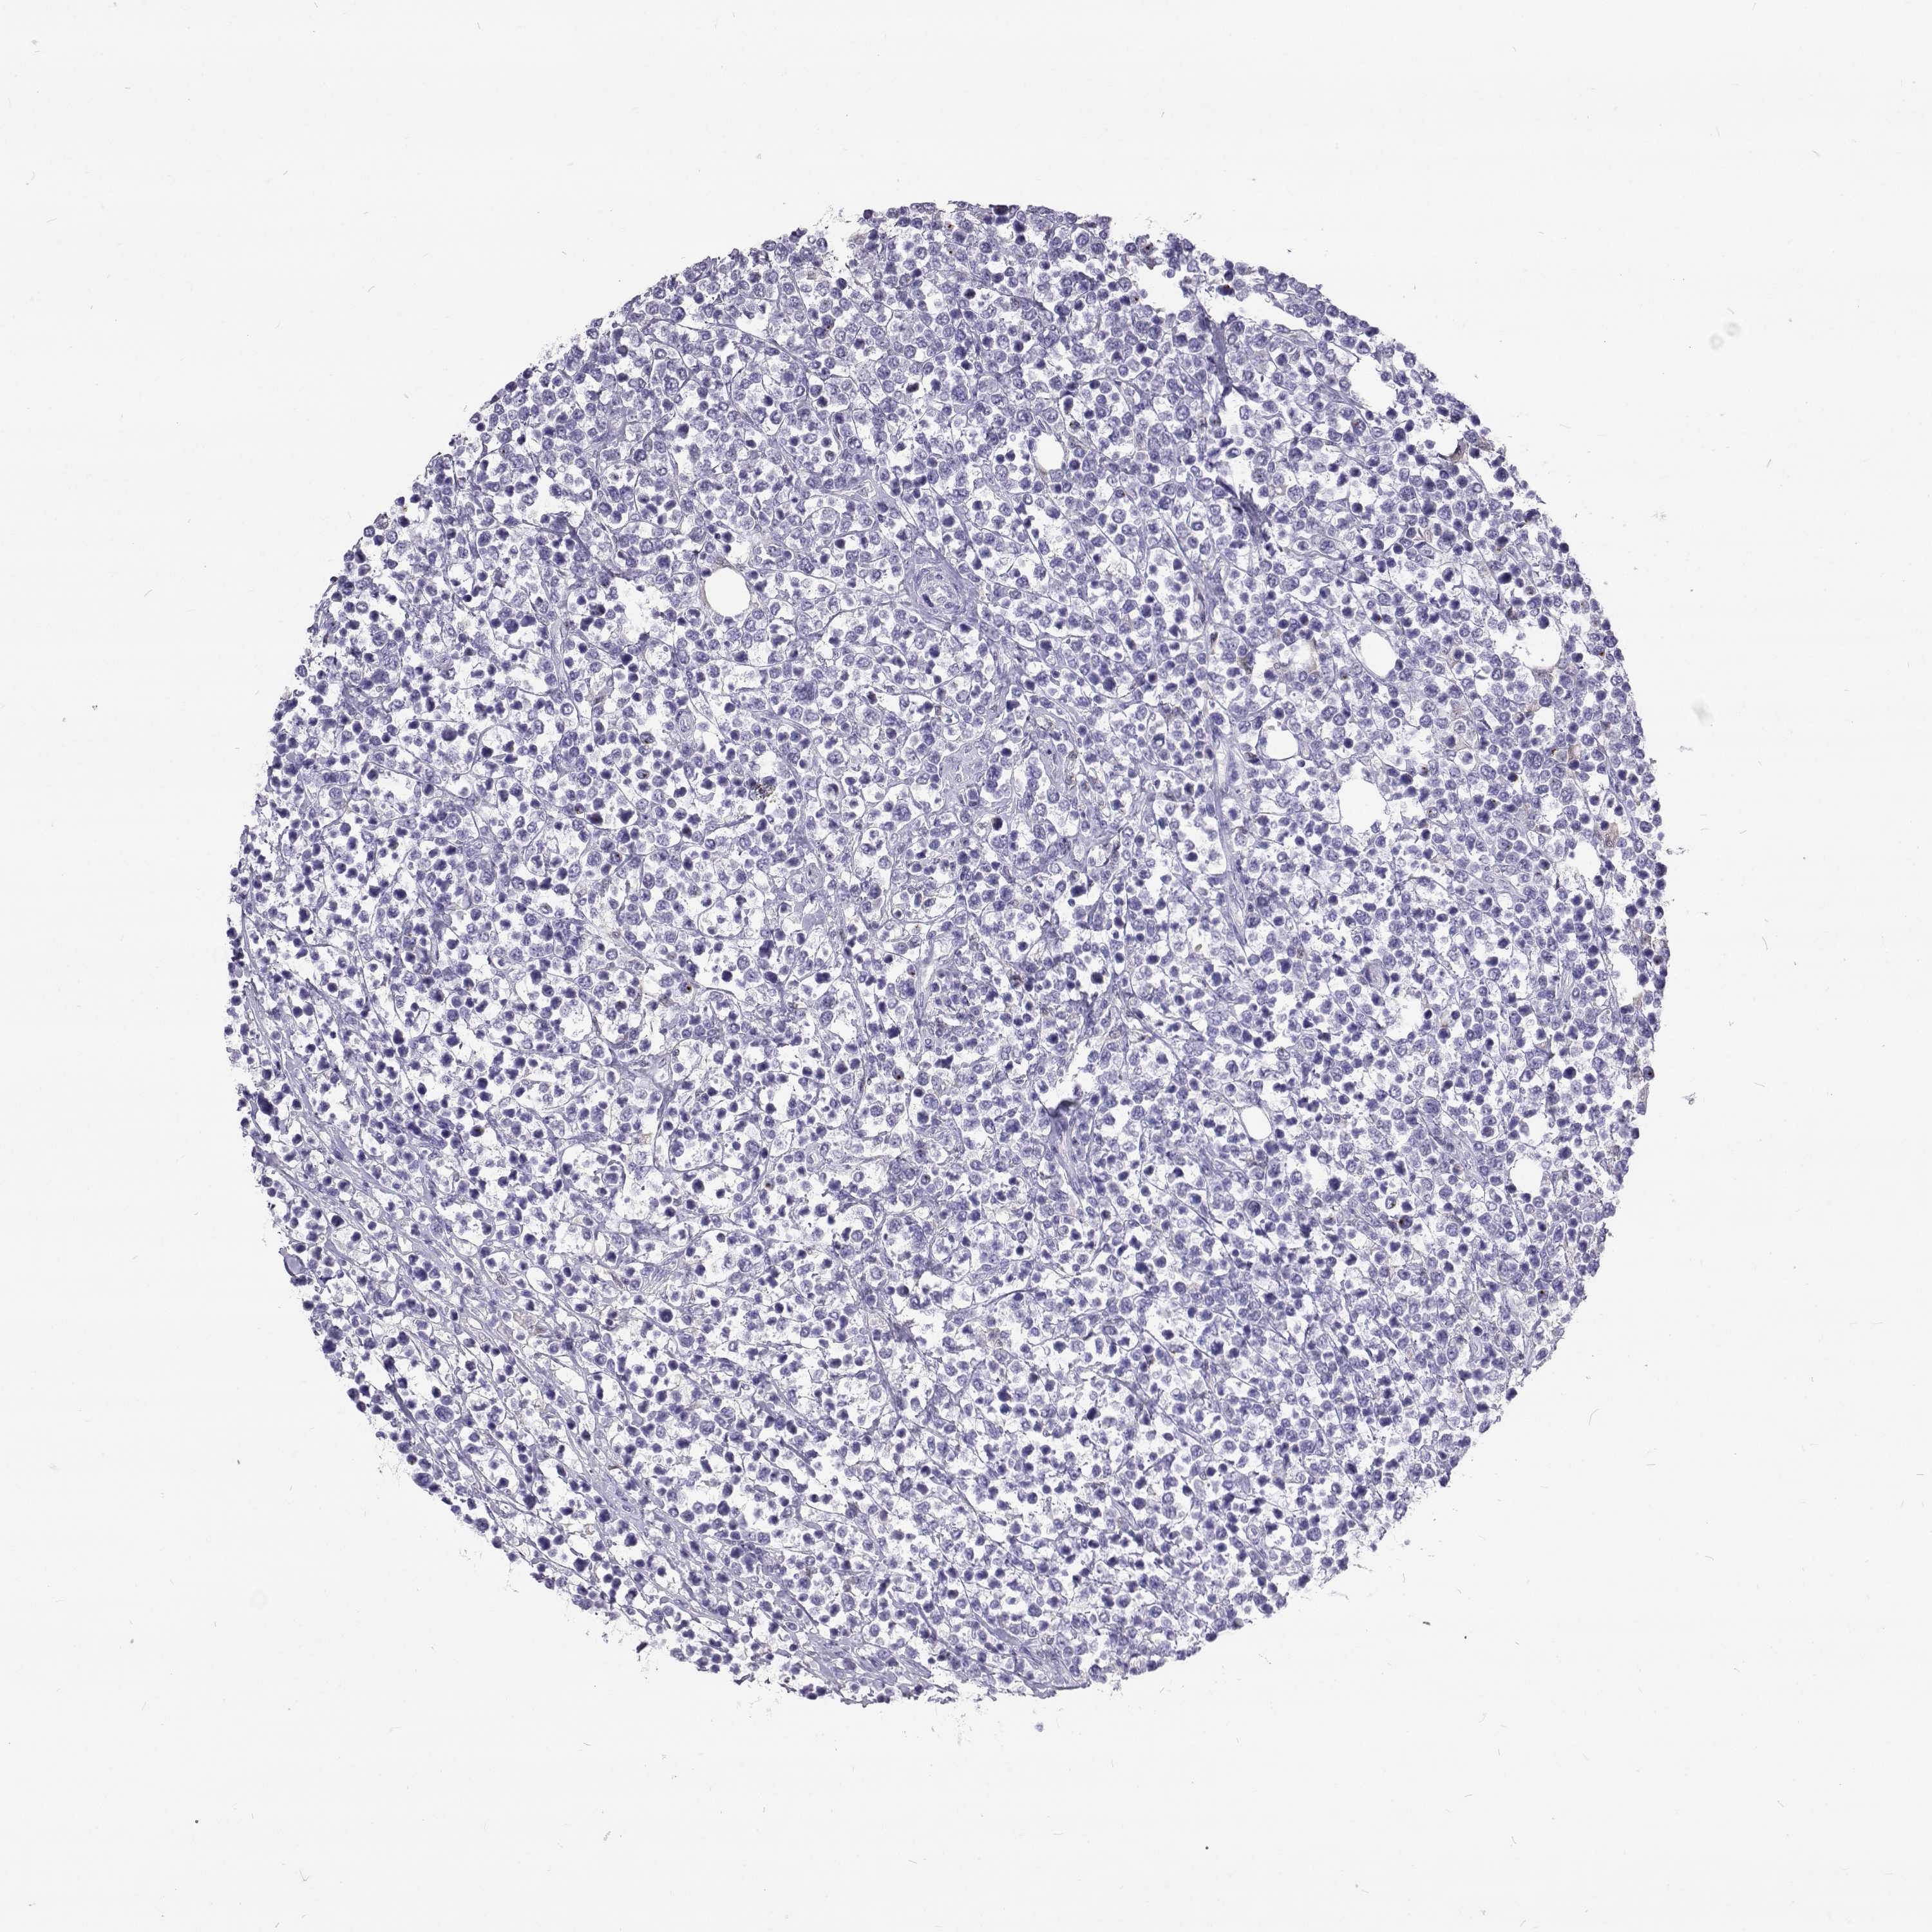

LYMPHOMA - Protein expressioni

A mouse-over function shows sample information and annotation data. Click on an image to view it in a full screen mode. Samples can be filtered based on level of antibody staining by selecting one or several of the following categories: high, medium, low and not detected. The assay and annotation is described here.

Antibody stainingi

Antibody staining in the annotated cell types in the current human tissue is reported as not detected, low, medium, or high, based on conventional immunohistochemistry profiling in selected tissues. This score is based on the combination of the staining intensity and fraction of stained cells.

Each image is clickable and will lead to virtual microscopy that enables deeper exploration of all samples and also displays staining intensity scores, fraction scores and subcellular localization as well as patient and tissue information for each sample.

Antibody HPA035472

Antibody HPA035473

Antibody HPA064835

Malignant lymphoma, non-Hodgkin's type, Low grade

Malignant lymphoma, non-Hodgkin's type, High grade

Hodgkin's disease, NOS